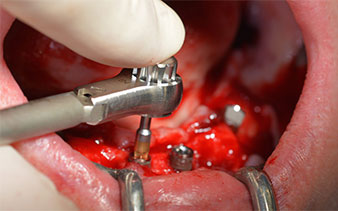

Ceci correspond à la position suivante prédéfinie dans l'Implantmed. Nous voyons ici le contre-angle W&H tenu à un angle de 45° par rapport à la crête dans la région de 45 afin de préserver le nerf mentonnier. Le trou mentonnier sert de repére anatomique à tous les forages de cette région. Les forages suivants ont été effectués à la vitesse réduite de 300 tr./min. (Fig. 10 et 11).

Le prochain réglage programmé est destiné à la mise en place des implants. Dans notre cabinet, nous appliquons généralement un couple de 32 Ncm pour cette phase (Fig. 12 et 13).